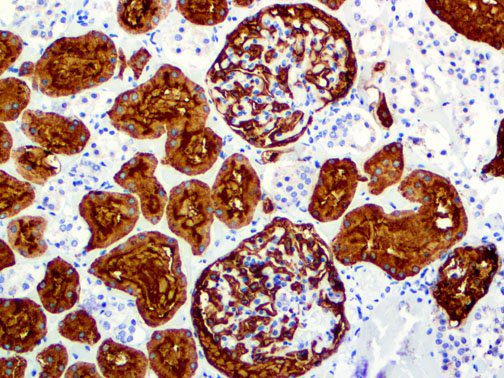

Clinical and laboratory manifestations of HLH include fever, enlarged liver and/or spleen, neurologic dysfunction, coagulopathy, liver dysfunction, cytopenias (i.e., low levels of erythrocytes, leukocytes, and/or platelets), hypertriglyceridemia, hyperferritinemia, hemophagocytosis, and eventually diminished NK cell activity as the immune system becomes progressively paralyzed. HLH can be familial (primary HLH) or secondary to another disease process (sHLH), such as rheumatic disease, in which it is referred to as macrophage activation syndrome (MAS, characterized by elevated ferritin).

This activation induces inflammatory monocytes to highly express IL-6, starting a localized and then systemic cascade effect that results in hyperproduction of IL-6, which accelerates the inflammatory process. Because IL-6 also increases vascular permeability, excessive levels cause blood vessels to become very leaky. This, along with clotting factors released from vascular endothelial cells, stimulates the coagulation cascade, resulting in microthrombosis (tiny clots), which leads to ischemia and tissue death of the kidney, intestines, heart, liver, brain and extremities.